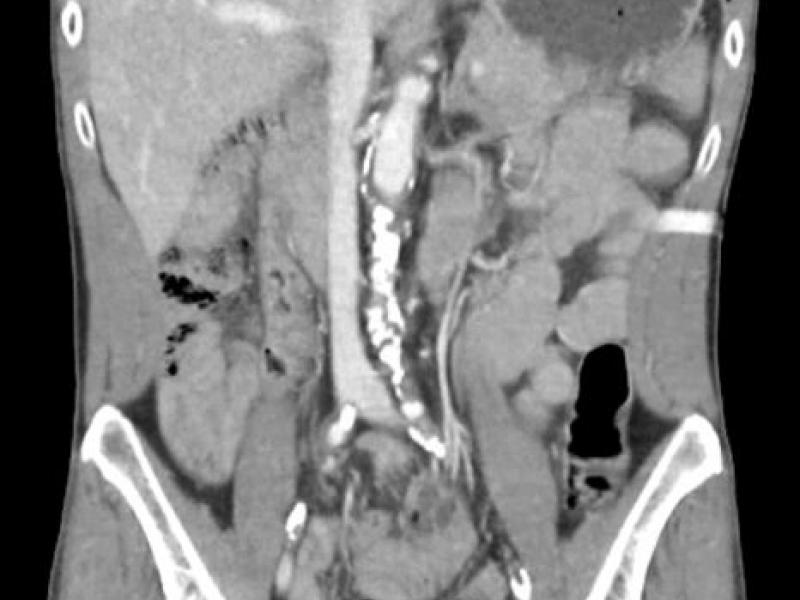

What's the diagnosis? By Dr. Angela Ugorets

A 64 yo female c/o dizziness. She has an unsteady gait